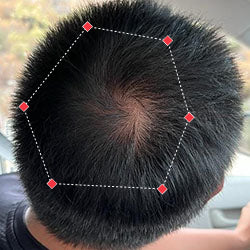

Indications for Use

The iRESTORE Hair Growth System Elite is indicated to promote hair growth in males who have Norwood-Hamilton Classifications of IIa to V and in females who have Ludwig-Savin Classifications I to II, and in both with Fitzpatrick Skin Phototypes I to IV. In other words, iRESTORE is not intended for people who are bald or have advanced hair loss.

Laser therapy works to reactivate thinning and dormant hairs. For completely bald areas of the scalp, there may be no way to promote hair regrowth. If you still have hair follicles, laser therapy may be beneficial to you.

Not sure? Email us to have our specialists evaluate your scalp conditions to see if iRESTORE is suitable for you.